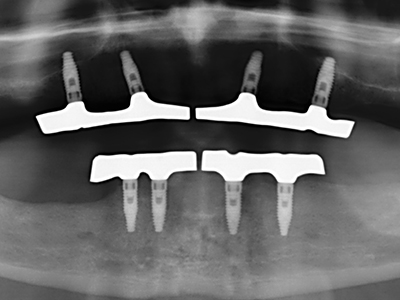

Fig. 11: la panoramica postoperatoria mostra l'accrescimento verticale e il rialzo del pavimento sinusale.

Fig. 14: posizionamento di quattro impianti RSX conici (BEGO Implant Systems, Brema).

Fig. 15: la radiografia dopo un follow up di un anno mostra condizioni stabili a livello osseo.